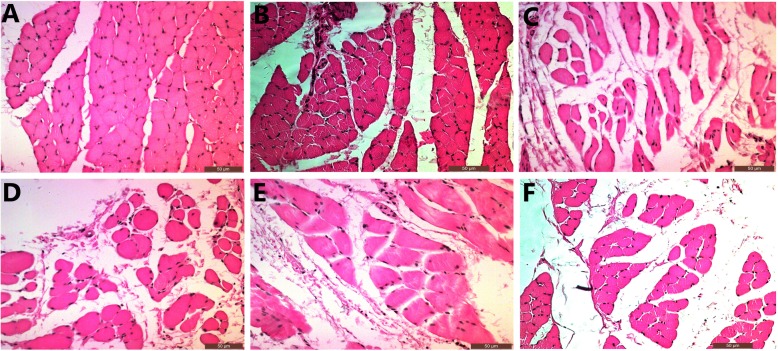

Cross-sectional area of the muscle fiber

FCR and DEL were biopsied from the affected side in Group A and B, respectively. Both of the two muscles were obtained in Group C and D. All the muscles were fixed in 10% paraformaldehyde (Shanghai Reagent Company, Shanghai, China). Then they were fixed in paraffin (Shanghai Reagent Company, Shanghai, China). The muscles were stained with hematoxylin and eosin(HE)(Shanghai Reagent Company, Shanghai, China). The mean cross-sectional area of the muscle fiber was measured and calculated by Image J system (National Institutes of Health, USA).

Cross-sectional area of the muscle fiber

We evaluated the mean cross-sectional areas of FCR and DEL muscle fibers to represent the recoveries of median and axillary nerves respectively. (Fig. 4) The average cross-sectional areas of FCR were 352.44 ± 71.33 μm2 in Group A and 327.71 ± 134.11 μm2 in Group C. There was no statistical difference between the two groups. Either the cross-sectional area in Group A or C was significantly larger than that in Group D (115.65 ± 19.46 μm2). The mean cross-sectional areas of DEL were 339.09 ± 117.69 μm2, 332.75 ± 111.54 μm2 and 261.61 ± 37.78 μm2 in Group B, C, D, respectively. There were no statistical differences among the three groups. (Fig. 5a).

Fig. 4.

a The cross-section of FCR muscle fibers in Group A. b The cross-section of FCR muscle fibers in Group C. c The cross-section of FCR muscle fibers in Group D. d The cross-section of DEL muscle fibers in Group B. e The cross-section of DEL muscle fibers in Group C. f The cross-section of DEL muscle fibers in Group D